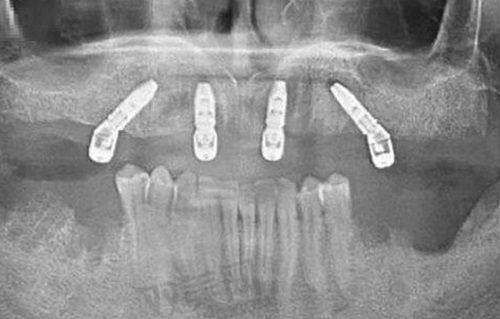

从市场情况来看,一口种植牙的价格范围跨度较大。单颗种植牙的价格可能从几千元到上万元不等,如果是全口种植牙,费用可能在数万元到数十万元。一些基础的全口种植牙方案可能相对便宜,但如果选择高端的种植体和牙冠材料,费用就会大幅上升。例如,一些进口的高端种植体,其本身的价格就比较昂贵,加上手术费、牙冠费等,全口的费用会相当可观。

种植体是种植牙的核心部分,不同品牌和种类的种植体价格差异明显。目前市场上有国产和进口的种植体,进口种植体一般价格较高,因为它们在研发、生产工艺等方面投入较大,质量和稳定性也相对较好。常见的进口种植体品牌有瑞士ITI、德国费亚丹等,而国产种植体在近年来也有了较大的发展,价格相对亲民。患者在选择种植体时,需要综合考虑自己的经济状况和口腔情况。

患者的口腔状况是影响全口种植牙费用的重要因素。如果患者的口腔健康状况良好,牙槽骨条件适宜,那么种植手术相对简单,费用也会相对较低。但如果患者存在牙周炎、牙槽骨骨量不足等问题,就需要精良行牙周治疗、骨增量手术等,这些额外的治疗会增加费用和治疗周期。例如,骨增量手术需要使用骨粉、骨膜等材料,这都会使整体费用上升。